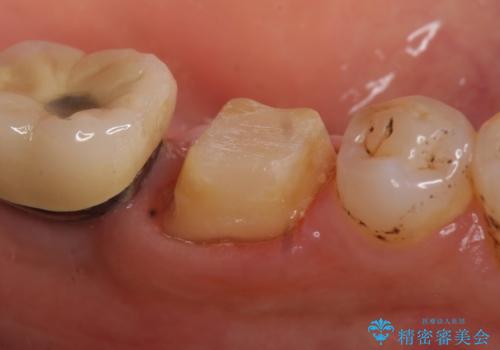

- 左下の奥歯で咬むと痛むので診て欲しいといらっしゃった方の症例です。

検査の結果、左下6番目の歯は神経が死んでおり根尖に病変が出来ていたため、根管治療を行いました。

その後症状の消失を確認後、オールセラミッククラウンによる補綴を行いました。